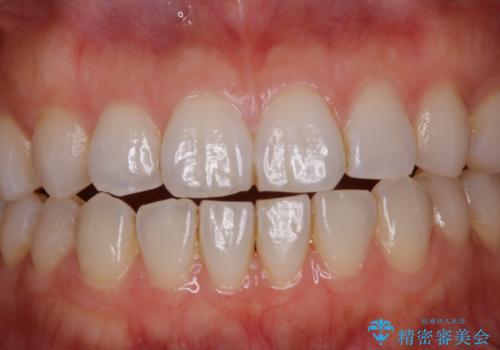

PMTCで見た目を綺麗に

- 専門的な機械ででしっかりとキレイにクリーニングしてほしいとのことでしたPMTC60分コースを行いました。

PMTCは、歯に付着した汚れを除去していくため、着色が気になる場合にも行うことができます。ご自身でのセルフケアだけで着色を落とそうとすると、逆に歯を傷つけてしまったり、精密に汚れを除去できないこともあります。また、日常生活で着色しやすい飲食物を避けたりすることはストレスに感じてしまったり、あまり現実的ではありません。

毎日丁寧に歯磨きをしていても、日常生活での飲食物などにより着色してしまうことはあります。PMTCでは、歯の表面の凸凹にミネラルを補給して、ツルツルの表面に仕上げます